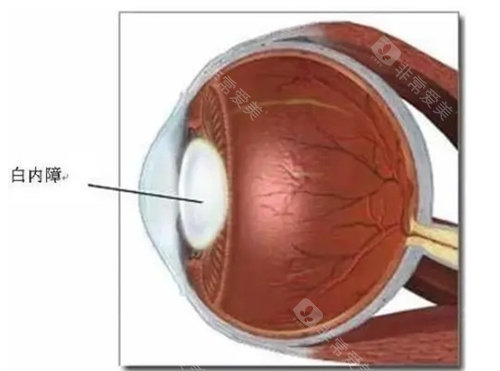

基于第七次国境内人口普查数据,呼市常住人口344.61万人,65岁以上老年群体占比达13.83%,总量约50万人。而中华医学组织眼科学分会的统计显示,我国60岁以上人群白内障发病率约80%,庞大的患病基数让政策延续成为民生刚需。

医学层面,申请者需经专科诊断确诊为白内障,且裸眼视力≤0.3或矫正视力<0.5,这一标准是判断手术必要性的核心依据。同时需排除相关禁忌症,例如活动性眼部感染、未控制的全身性疾病等。